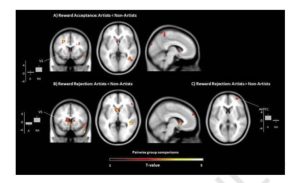

Исследование: мозг творческих людей мешает им зарабатывать